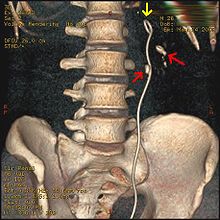

Ureteroscopy has become increasingly popular as flexible and rigid fiberoptic ureteroscopes have become smaller. One ureteroscopic technique involves the placement of a ureteral stent (a small tube extending from the bladder, up the ureter and into the kidney) to provide immediate relief of an obstructed kidney. Stent placement can be useful for saving a kidney at risk for postrenal acute kidney failure due to the increased hydrostatic pressure, swelling and infection (pyelonephritis and pyonephrosis) caused by an obstructing stone. Ureteral stents vary in length from 24 to 30 cm (9.4 to 11.8 in) and most have a shape commonly referred to as a "double-J" or "double pigtail", because of the curl at both ends. They are designed to allow urine to flow past an obstruction in the ureter. They may be retained in the ureter for days to weeks as infections resolve and as stones are dissolved or fragmented by ESWL or by some other treatment. The stents dilate the ureters, which can facilitate instrumentation, and they also provide a clear landmark to aid in the visualization of the ureters and any associated stones on radiographic examinations. The presence of indwelling ureteral stents may cause minimal to moderate discomfort, frequency or urgency incontinence, and infection, which in general resolves on removal. Most ureteral stents can be removed cystoscopically during an office visit under topical anesthesia after resolution of urolithiasis.[102]

Measurement of a 5.6 mm large kidney stone in soft tissue versus skeletal CT window.

Bilateral staghorn calculi as seen on CT